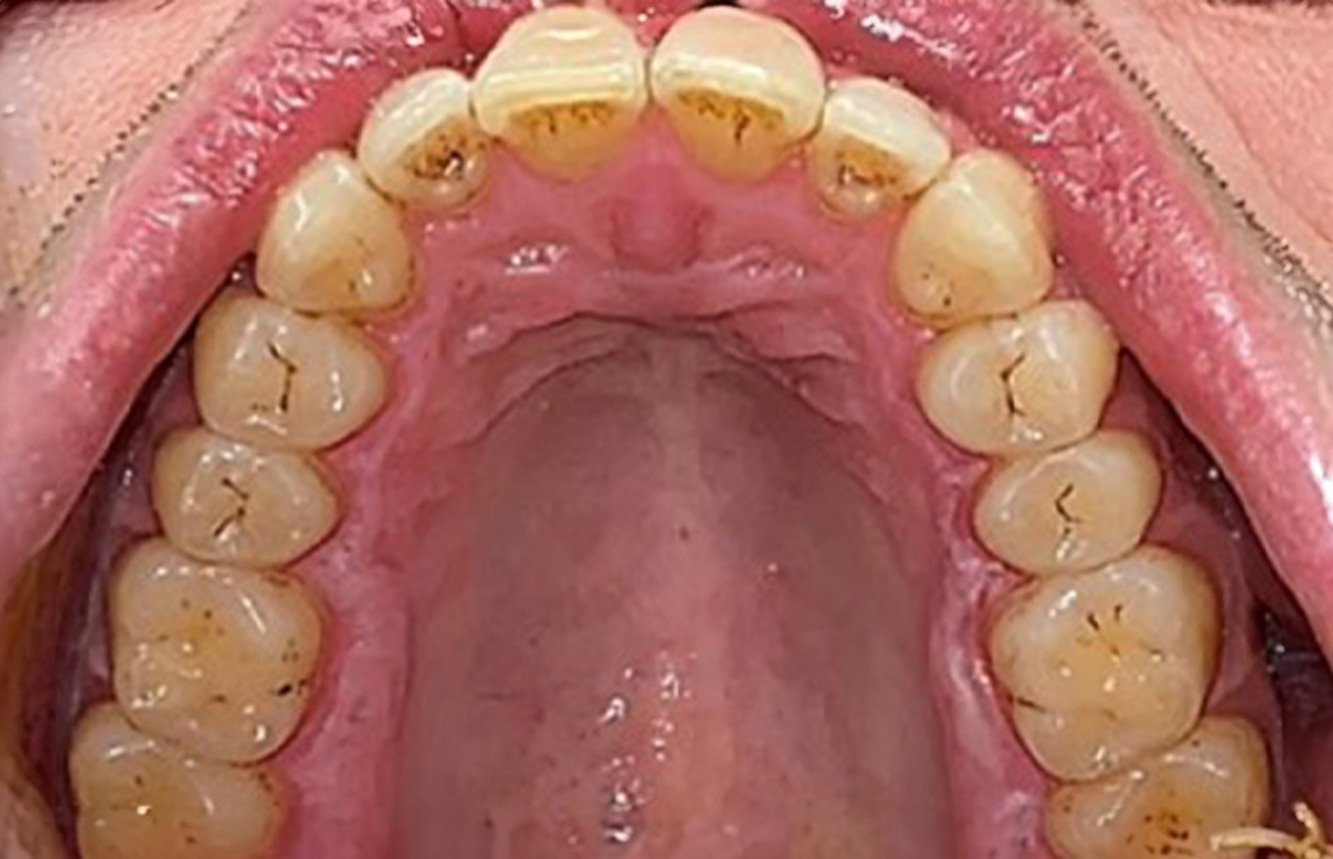

Paciente de trasplante con hiperplasia gingiva

Se presenta un paciente de 71 años con trasplante de riñón e hipertensión (presión arterial alta). Debido a su historia médica, es necesario el tratamiento continuo con ciclosporina para suprimir el sistema inmunitario y amlopidina para bajar la presión arterial. Además, el paciente relata encías sensibles y sangrantes. Desde el punto de vista de la salud oral, hay dientes restaurados con ocho piezas faltantes, hiperplasia gingival pronunciada, periodontitis en fase II, de grado B con bolsas activas y una caries inicial en la pieza 22. En la evaluación del riesgo de caries se ha establecido un riesgo de caries medio (API 60). Para la sesión de profilaxis se hacen las siguientes recomendaciones. más información